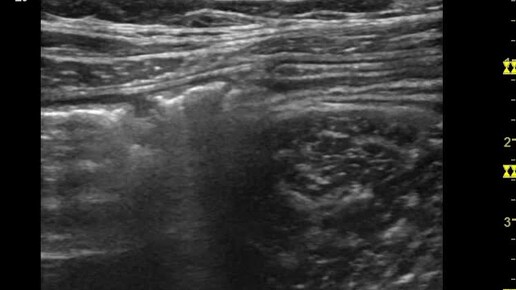

Ультразвуковые находки от врача УЗД Зорина Я.П.